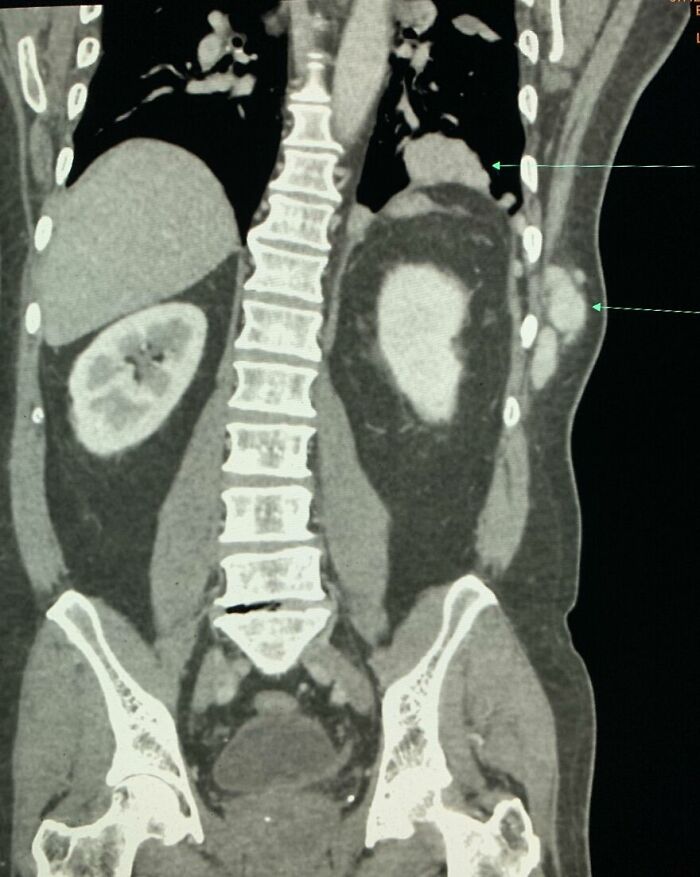

#4 Accessory Organs

People being born with extra parts isn’t uncommon, but most don’t know they might have extra organs. Approximately 30% of people actually have these accessory organs and don’t find out until something goes wrong with them. Oddly, they’re not useless because they function the same as the original, just in a different space.

The spleen is one of the most common accessory organs. Per Springer Nature Link, it’s usually benign, but may mimic a tumor or enlarged lymph node. Accessory livers and pancreases are also common. Most additional organs can cause similar confusion, though they’re primarily unexplainable anatomical variations.

From an evolutionary perspective, they’re developmental leftovers that form when tissues split or migrate oddly during early growth. Now, they can be left alone, although in rare cases, an accessory organ can compensate if the main one is damaged or removed.